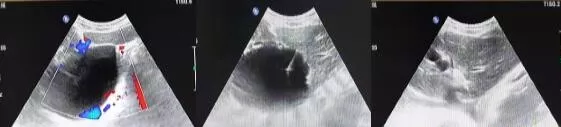

介入超声

介入超声:超声引导下进行的微创诊疗措施,开展了超声引导下穿刺活检、置管引流、穿刺引流等。